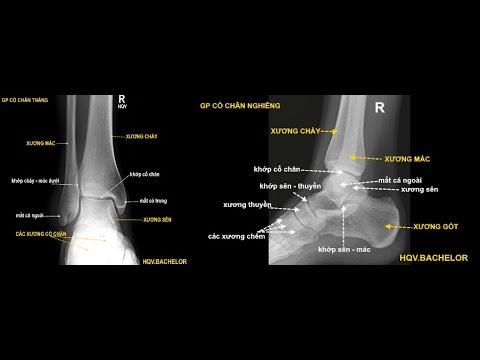

Cấu trúc giải phẫu học vùng cổ chân. Ba xương tạo nên khớp cổ chân gồm: Xương chày: một trong hai xương cẳng chân, chịu sức chính ở cẳng chân. Xương mác: là xương cẳng chân thứ hai. Và xương sên: một

Oct 21, 2022Các xương cổ chân. Gồm 7 xương sắp xếp thành hai hàng: Hàng sau: tất cả hai xương là xương sên với xương gót. Hàng trước: tất cả 5 xương là xương ghe, xương vỏ hộp và ba xương chêm. Xương

Bàn chân và cổ chân tạo nên một cấu trúc giải phẫu phức tạp bao gồm 26 xương hình dạng không đều, 30 khớp hoạt dịch, hơn 100 dây chằng và 30 cơ tác động lên các phân đoạn. Tất cả các khớp phải tương t